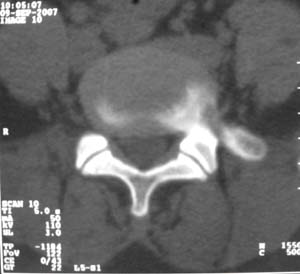

标题: CT9676:女,34岁,腰5骶1右侧神经根增粗?请各位老师会诊! [打印本页]

标题: CT9676:女,34岁,腰5骶1右侧神经根增粗?请各位老师会诊!

女,34岁,腰背部及右下肢酸痛两年余.